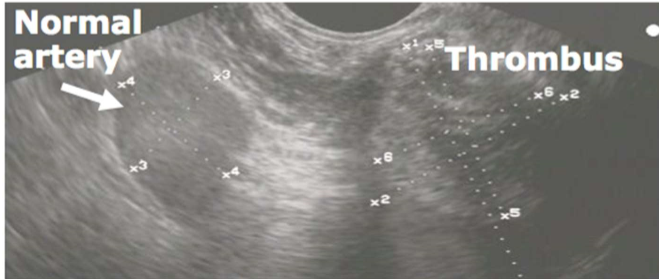

• Ultrasonography is used to confirm the diagnosis of jugular thrombosis and allows…

• Assessment of the extent of the thrombus

• Identification of sepsis (cavitation)

• Assessment of the patency of the vein (i.e., is there blood flow or a complete obstruction)

• Distinguishing perivenous swelling from thrombosis

• Selection of the site for aspiration (for culture)

• Visualisation of the thrombus with transrectal ultrasonography (blood is not anechoic due to the cellular content)

• The thrombus is in a distended vessel and the appearance is more hyperechoic than normal